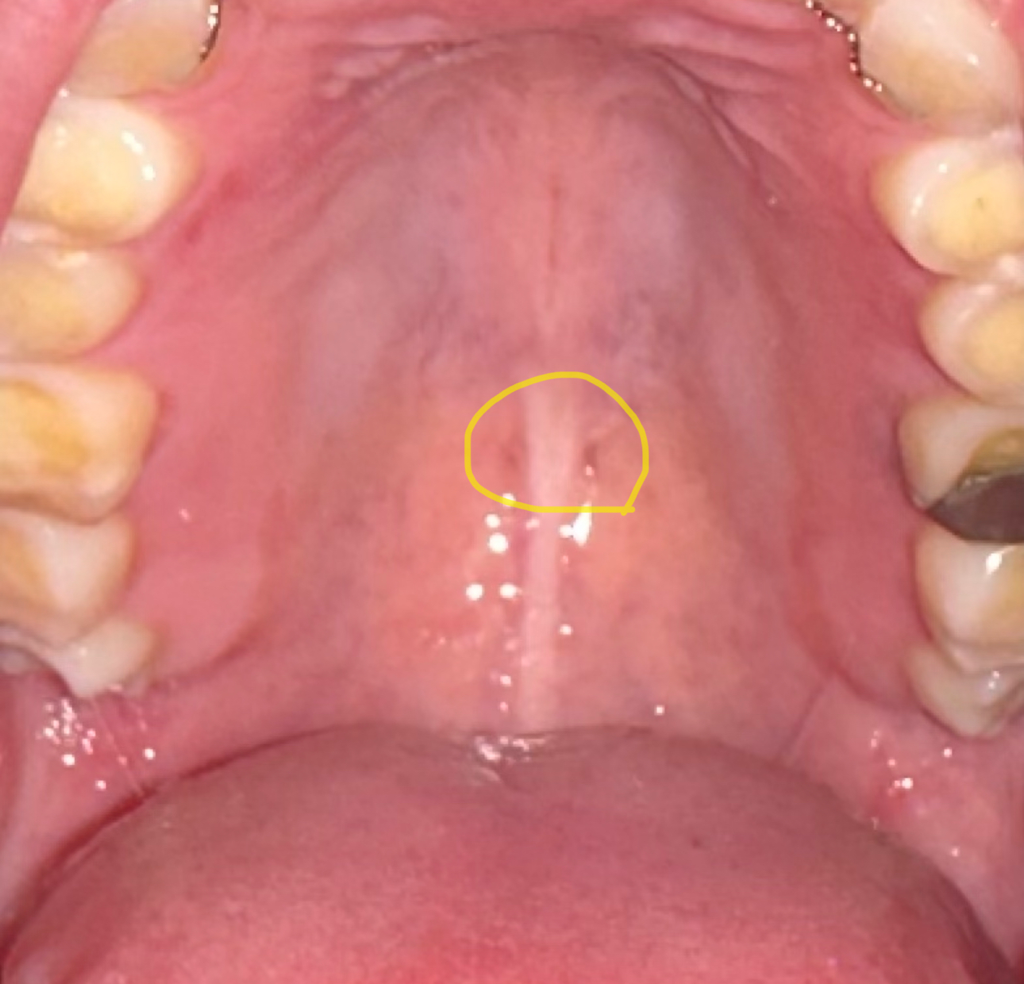

그래서 조금 전 휴대폰 후레쉬로 제 입속을 들여다봤는데 사진과 같이 입천장에 검정색 점이 대칭으로 두개씩이나 있어서 혹시나 구강암의 증상이 아닐까 싶어 질문 남깁니다.

통증은 없으나 구강암을 비롯한 두경부암 증상이 사진처럼 구강(입천장)에 검정색 점이 나타나는 양상을 보이기도 하나요?

• 2번 째 사진

점이라고 표현 하긴 했지만 원래 있는 구멍입니다.

해부학적으로 이상이 없는것이니 걱정하지 않고 지내셔도 됩니다.

대칭적이라면 혈관 등이 점막에 의해 비치는 것일 가능성이 있습니다.

암의 가능성은 매우 낮습니다. 하지만 걱정이 되신다면 이비인후과 등에서 정확한 진단을 받아보시는 것이 좋겠습니다.